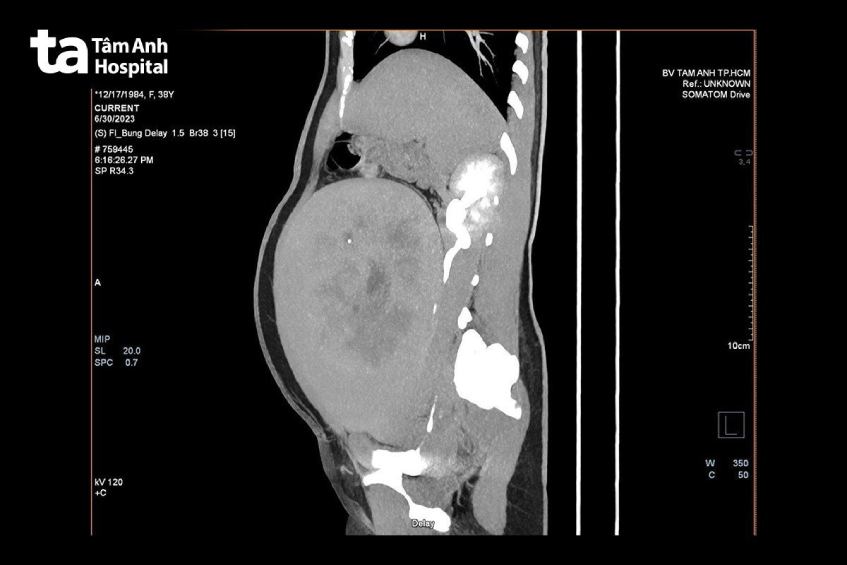

Tại đây, kết quả siêu âm cho thấy huyết khối kèm u xơ tử cung rất lớn, to bằng thai 30 tuần, thiếu máu nặng. Xét nghiệm máu, chỉ số hemoglobin còn 7g/dl (nữ bình thường là 12.5 – 14.2g/dl), phải truyền máu khẩn cấp. Người bệnh được chỉ định CT tiêm thuốc cản quang phát hiện, u xơ tử cung chèn ép dãn niệu quản và ứ nước thận phải, có huyết khối ở tĩnh mạch 2 chân, có huyết khối trong động mạch phổi.

BS CKII Nguyễn Bá Mỹ Nhi, Giám đốc Trung tâm Sản Phụ khoa, BVĐK Tâm Anh TP HCM cho biết, bác sĩ sản khoa và tim mạch hội chẩn, xác định sức khỏe chị Mai nguy hiểm do hiệu ứng chèn ép của khối u xơ lớn, dẫn đến ứ trệ tĩnh mạch vùng chậu và hai chi dưới, hình thành huyết khối, nguyên nhân chính gây thuyên tắc mạch phổi với triệu chứng khó thở. Nếu không điều trị, người bệnh có thể đột tử.